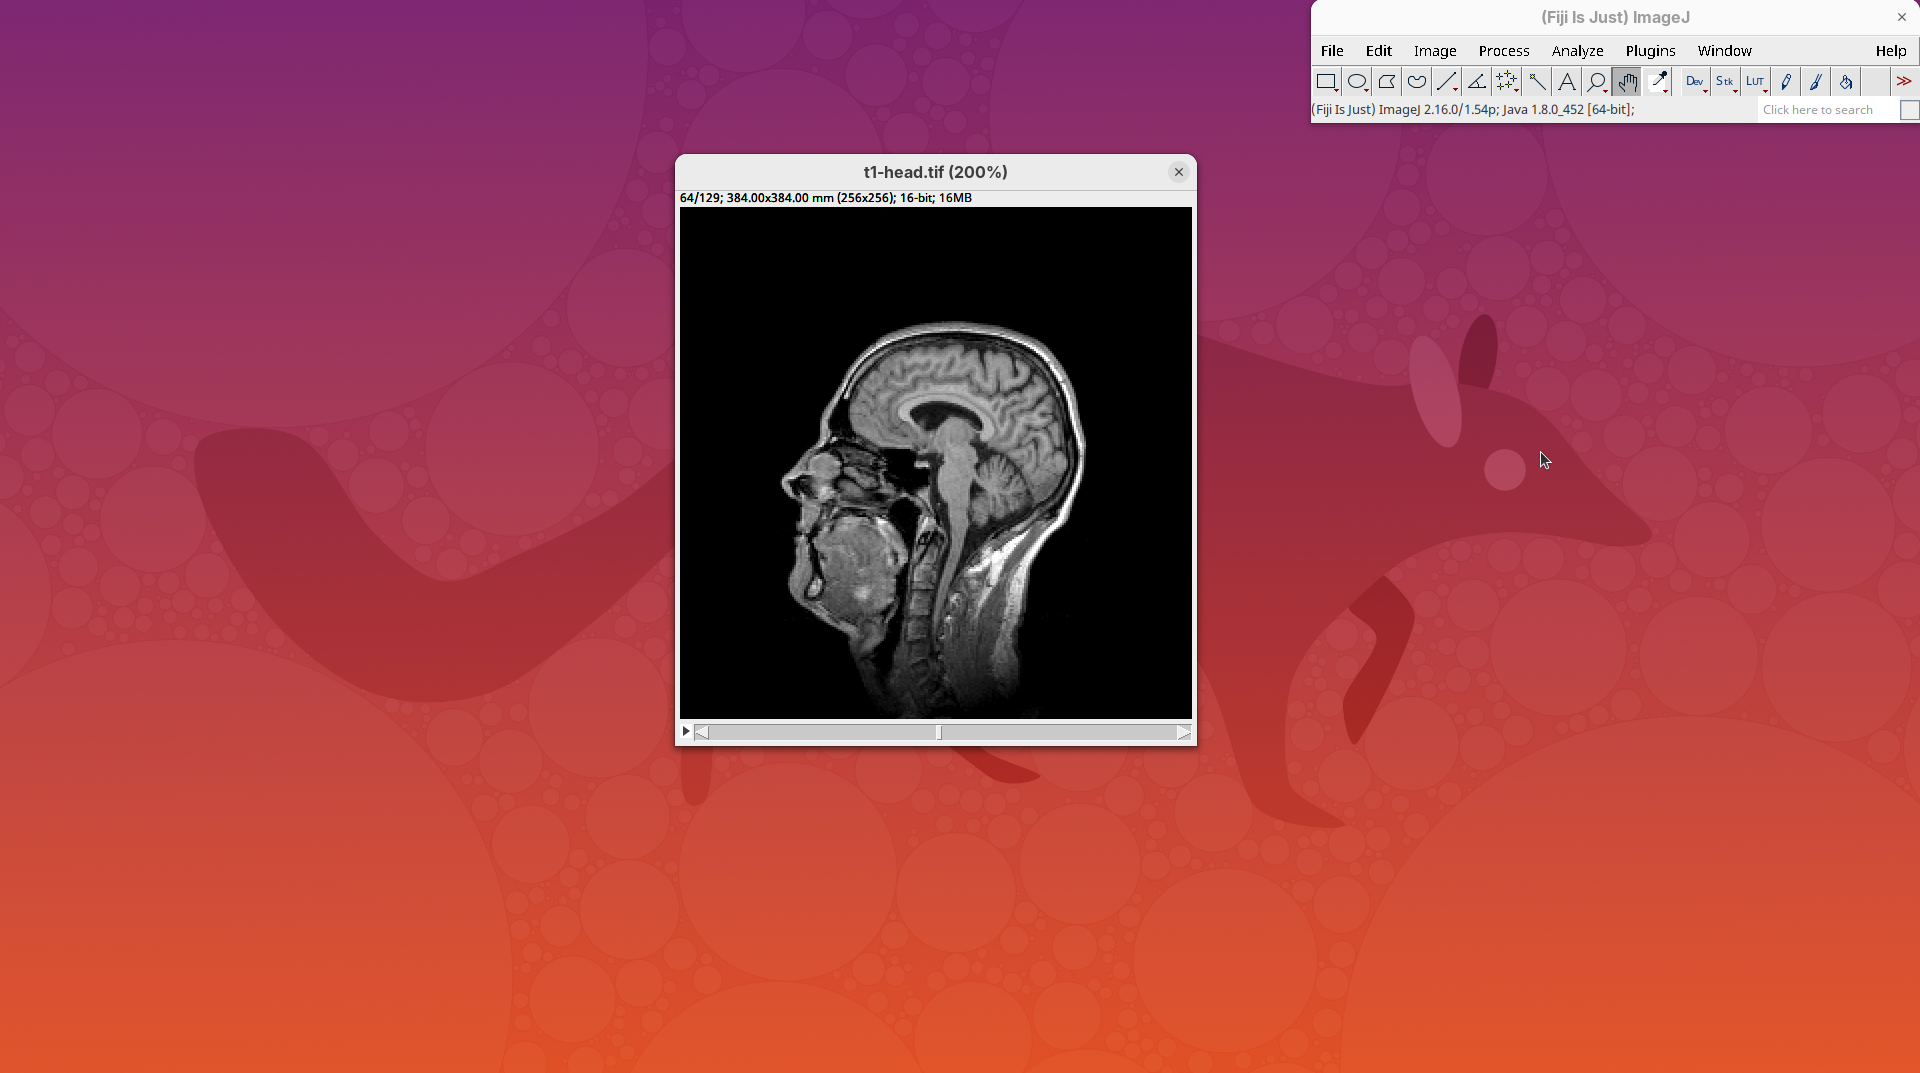

- Increase the zoom to 200% for better visualization.

Orthogonal Views

Orthogonal Views is a tool that shows the optical sections through the orthogonal planes of XY: XZ and YZ. It is an easy and quick way to get a sense of the tridimensionality of your dataset. Whenever I’m opening a dataset for the first time I use Orthogonal Views. To activate it:

- Click on

Image>Stacks>Orthogonal Views(or pressCtrl+Shift+H). - The XZ and YZ panels will open next to your XY stack.

- The yellow lines are synchronized between the panels.

- Click around the different parts of the head to inspect the same position under different angles.

Orthogonal Views is a great way to start understanding your 3D data.